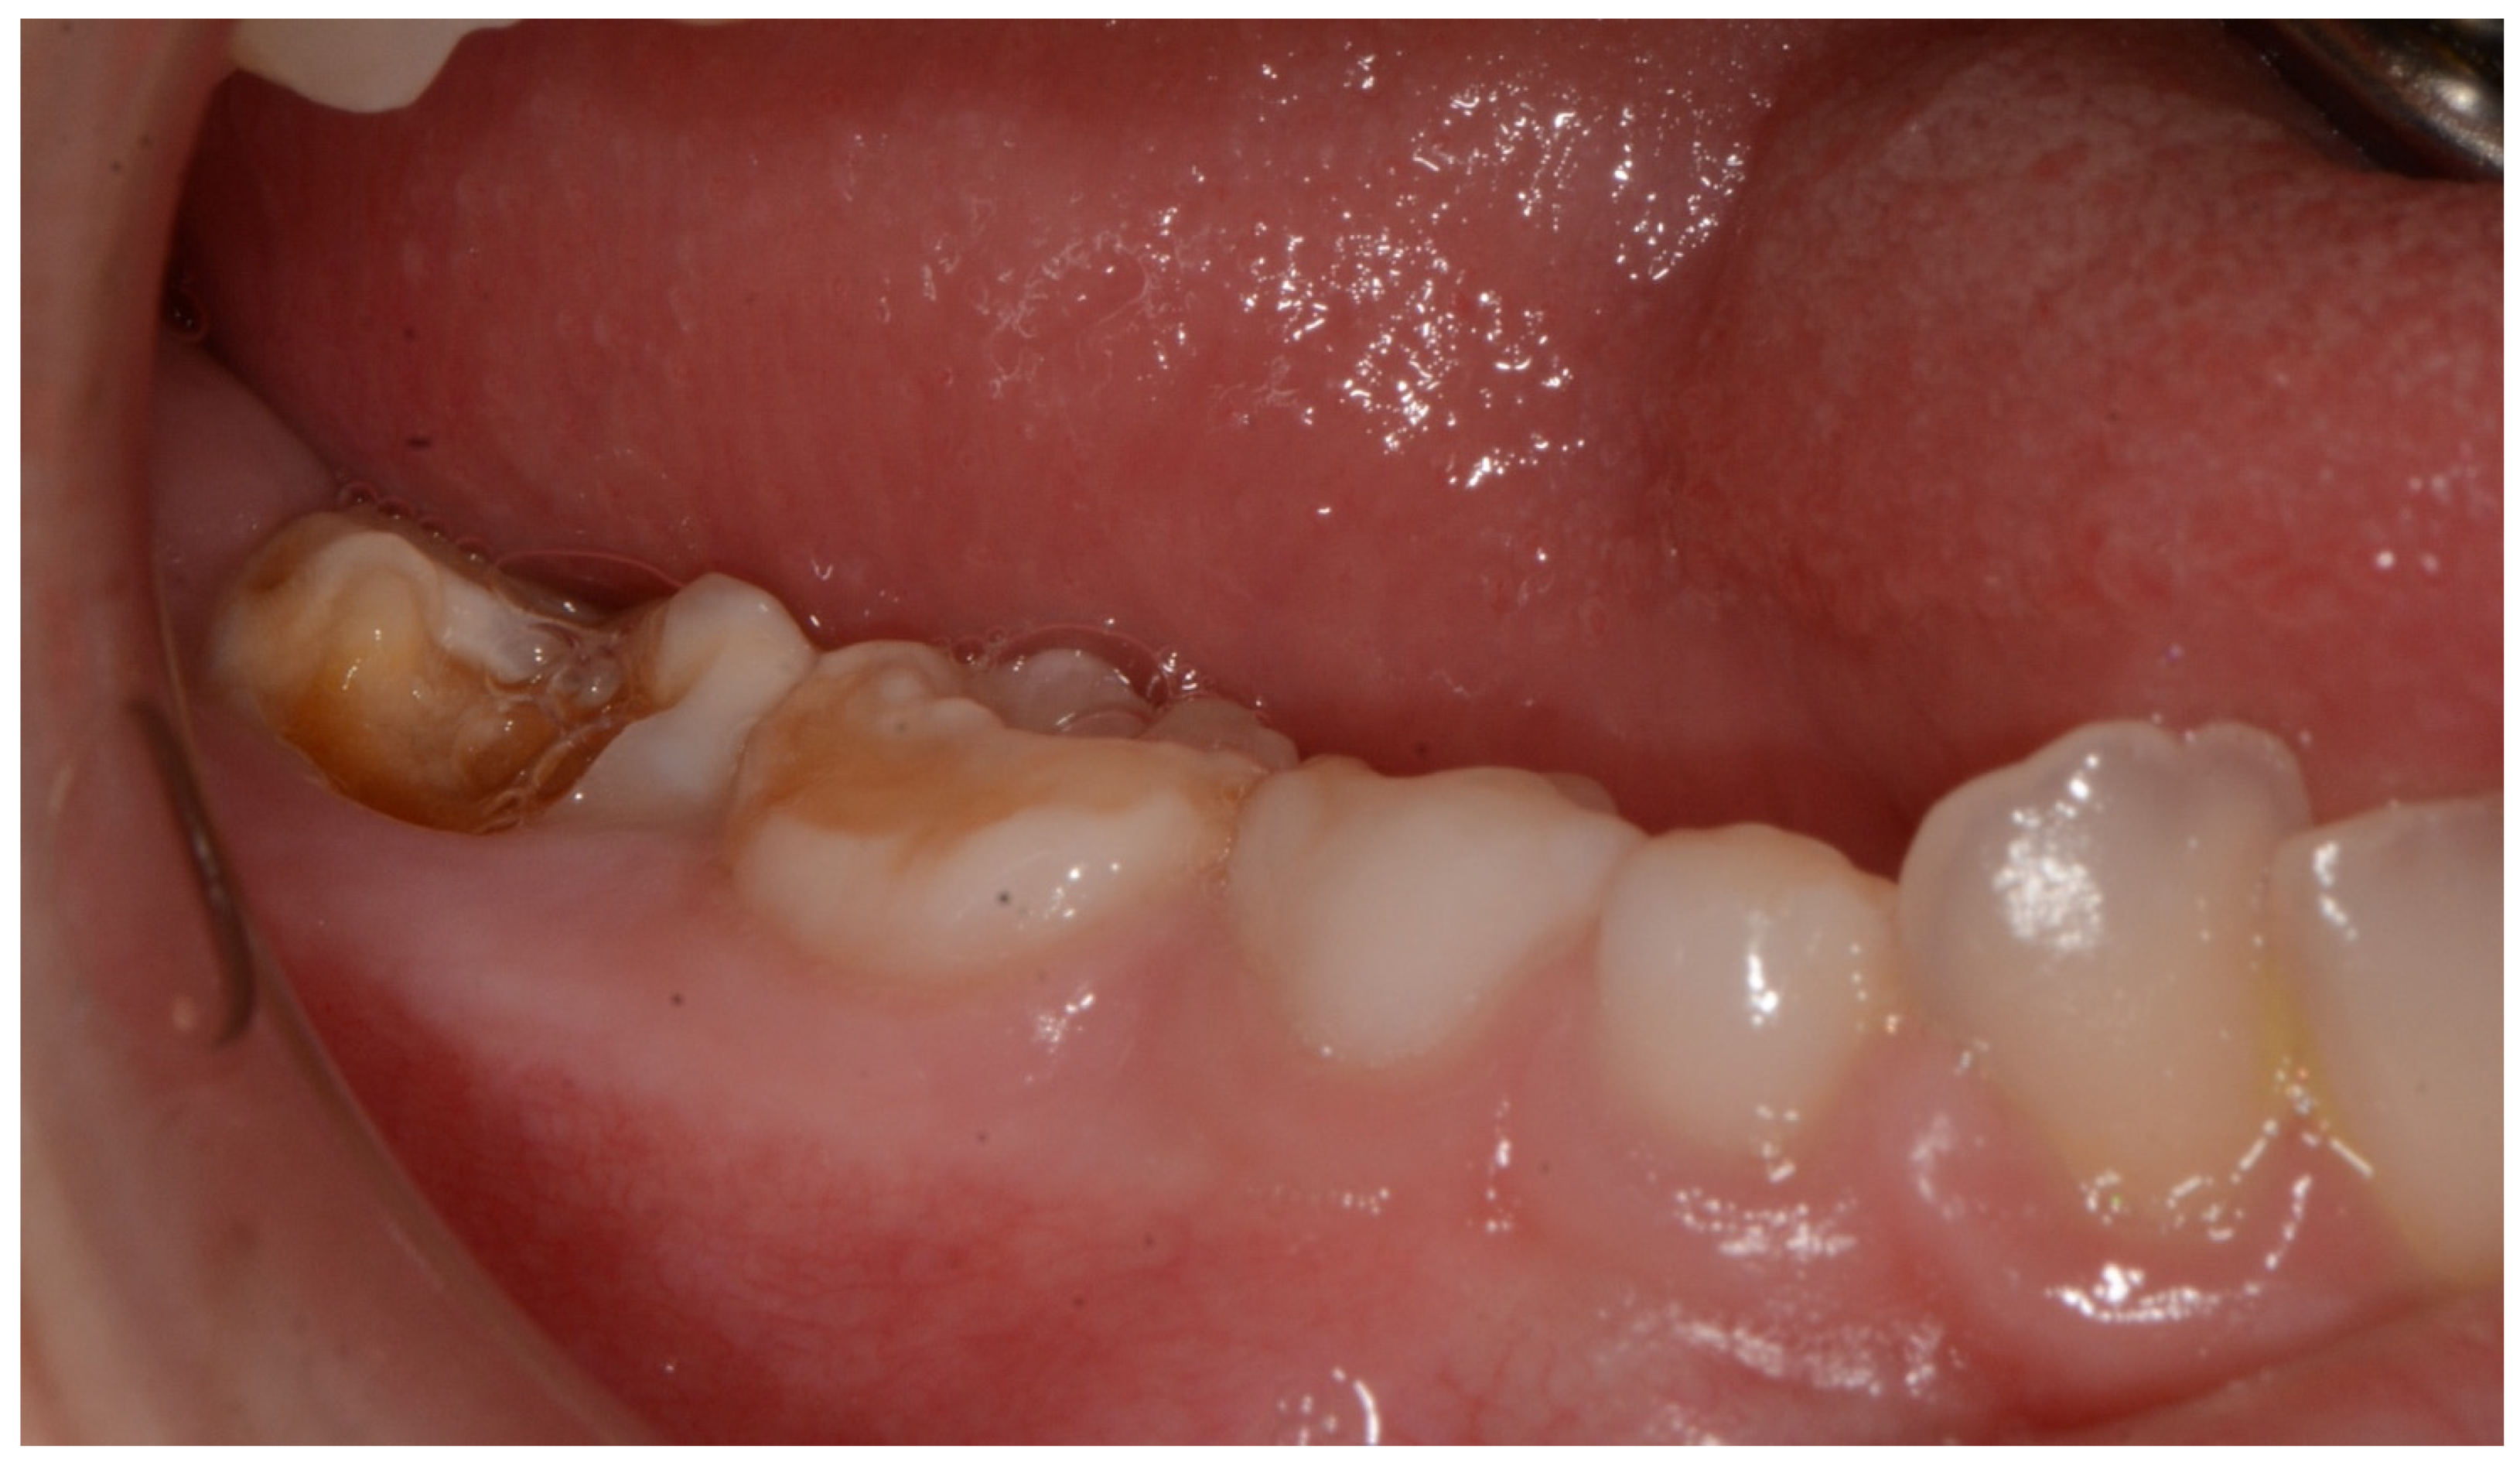

| Pascolini et al., 2018 | Patient n.2 | F | small mouth, dental anomalies with multiple caries. | 3.9 |

| Present study 2021 | 1 patient | M | high narrow palate, crowding, molar incisor hypomineralization (MIH), second class | 9 |